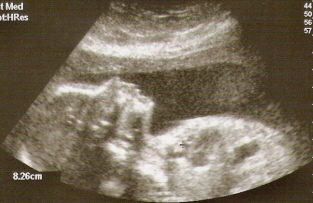

אבל עכשיו, טפו-טפו, מותר כבר לספר, ואפילו להתגאות, ולכן קבלו במחיאות כפיים סוערות בהופעת בכורה עולמית: הרודניסימה!